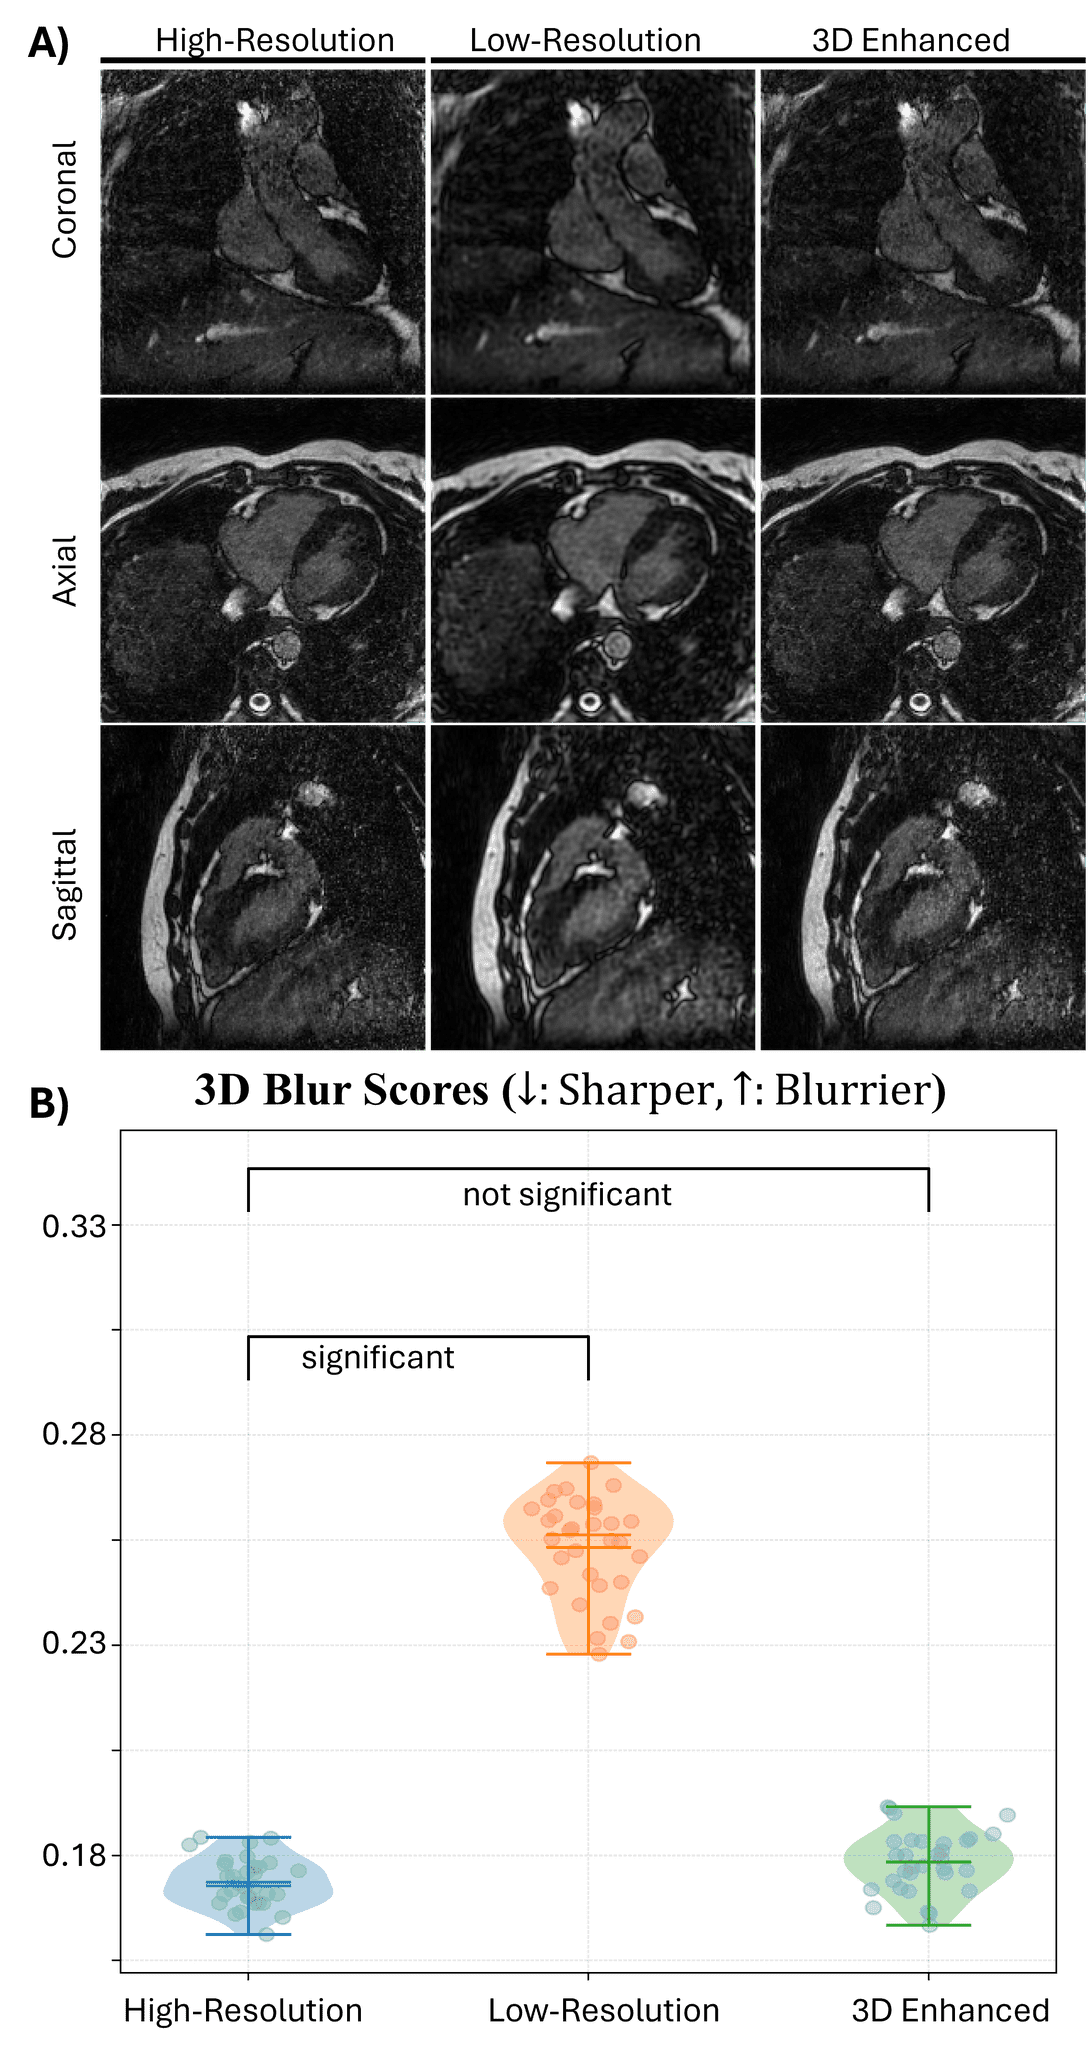

Figure 2: Retrospective evaluation of 3D-enhanced image quality compared to low- and high-resolution images. (A) Axial, sagittal, and coronal slices from a held-out subject show visual comparisons between high-resolution, low-resolution, and 3D-enhanced images. The 3D enhanced images reconstructed from 50% undersampled low-resolution data demonstrate close resemble to high-resolution images. (B) Quantitative sharpness analysis using a no-reference blur metric shows that 3D enhanced images have blur scores statistically indistinguishable from high-resolution images (P = 0.081), while low-resolution images show significantly degraded sharpness compared to high-resolution (P < 0.001).